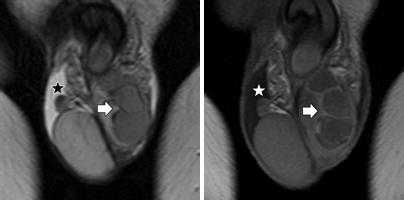

а, b Несеминомная опухоль левого яичка. МРТ. Образование с жидкостными включениями (звездочка). Нормальное правое яичко: (а) Фронтальное Т2-взвешенное изображение; (b) Аксиальное контрастно-усиленное Т1 -взвешенное изображение с насыщением жировой ткани.

Опухоли яичек наиболее часто встречается в возрасте 15-40 лет.

Небольшое правостороннее гидроцеле (*). Септальное строение опухоли, выявляемое при внутривенном контрастировании.

Левосторонняя семинома с инвазией левого семенного канатика.

Липома семенного канатика, гидроцеле

Гематома правого семенного канатика после впарвления паховой грыжи.

Варикоцеле (стрелка) и гидроцеле (*) слева.